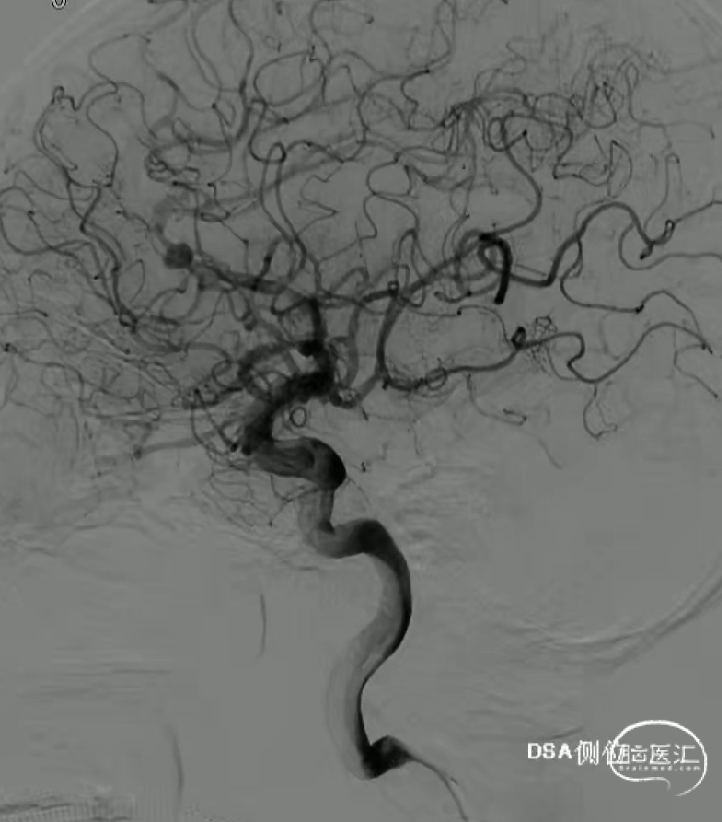

术前影像

· 患者三型弓,奇大脑前A3段动脉瘤,形态极不规则,血管入路极其迂曲

· 从大脑前动脉瘤起始段,有广泛伴有动脉粥样硬化的斑块

手术过程

术后即刻造影,动脉瘤滞留明显,载瘤动脉管腔通畅无狭窄,支架贴壁理想。